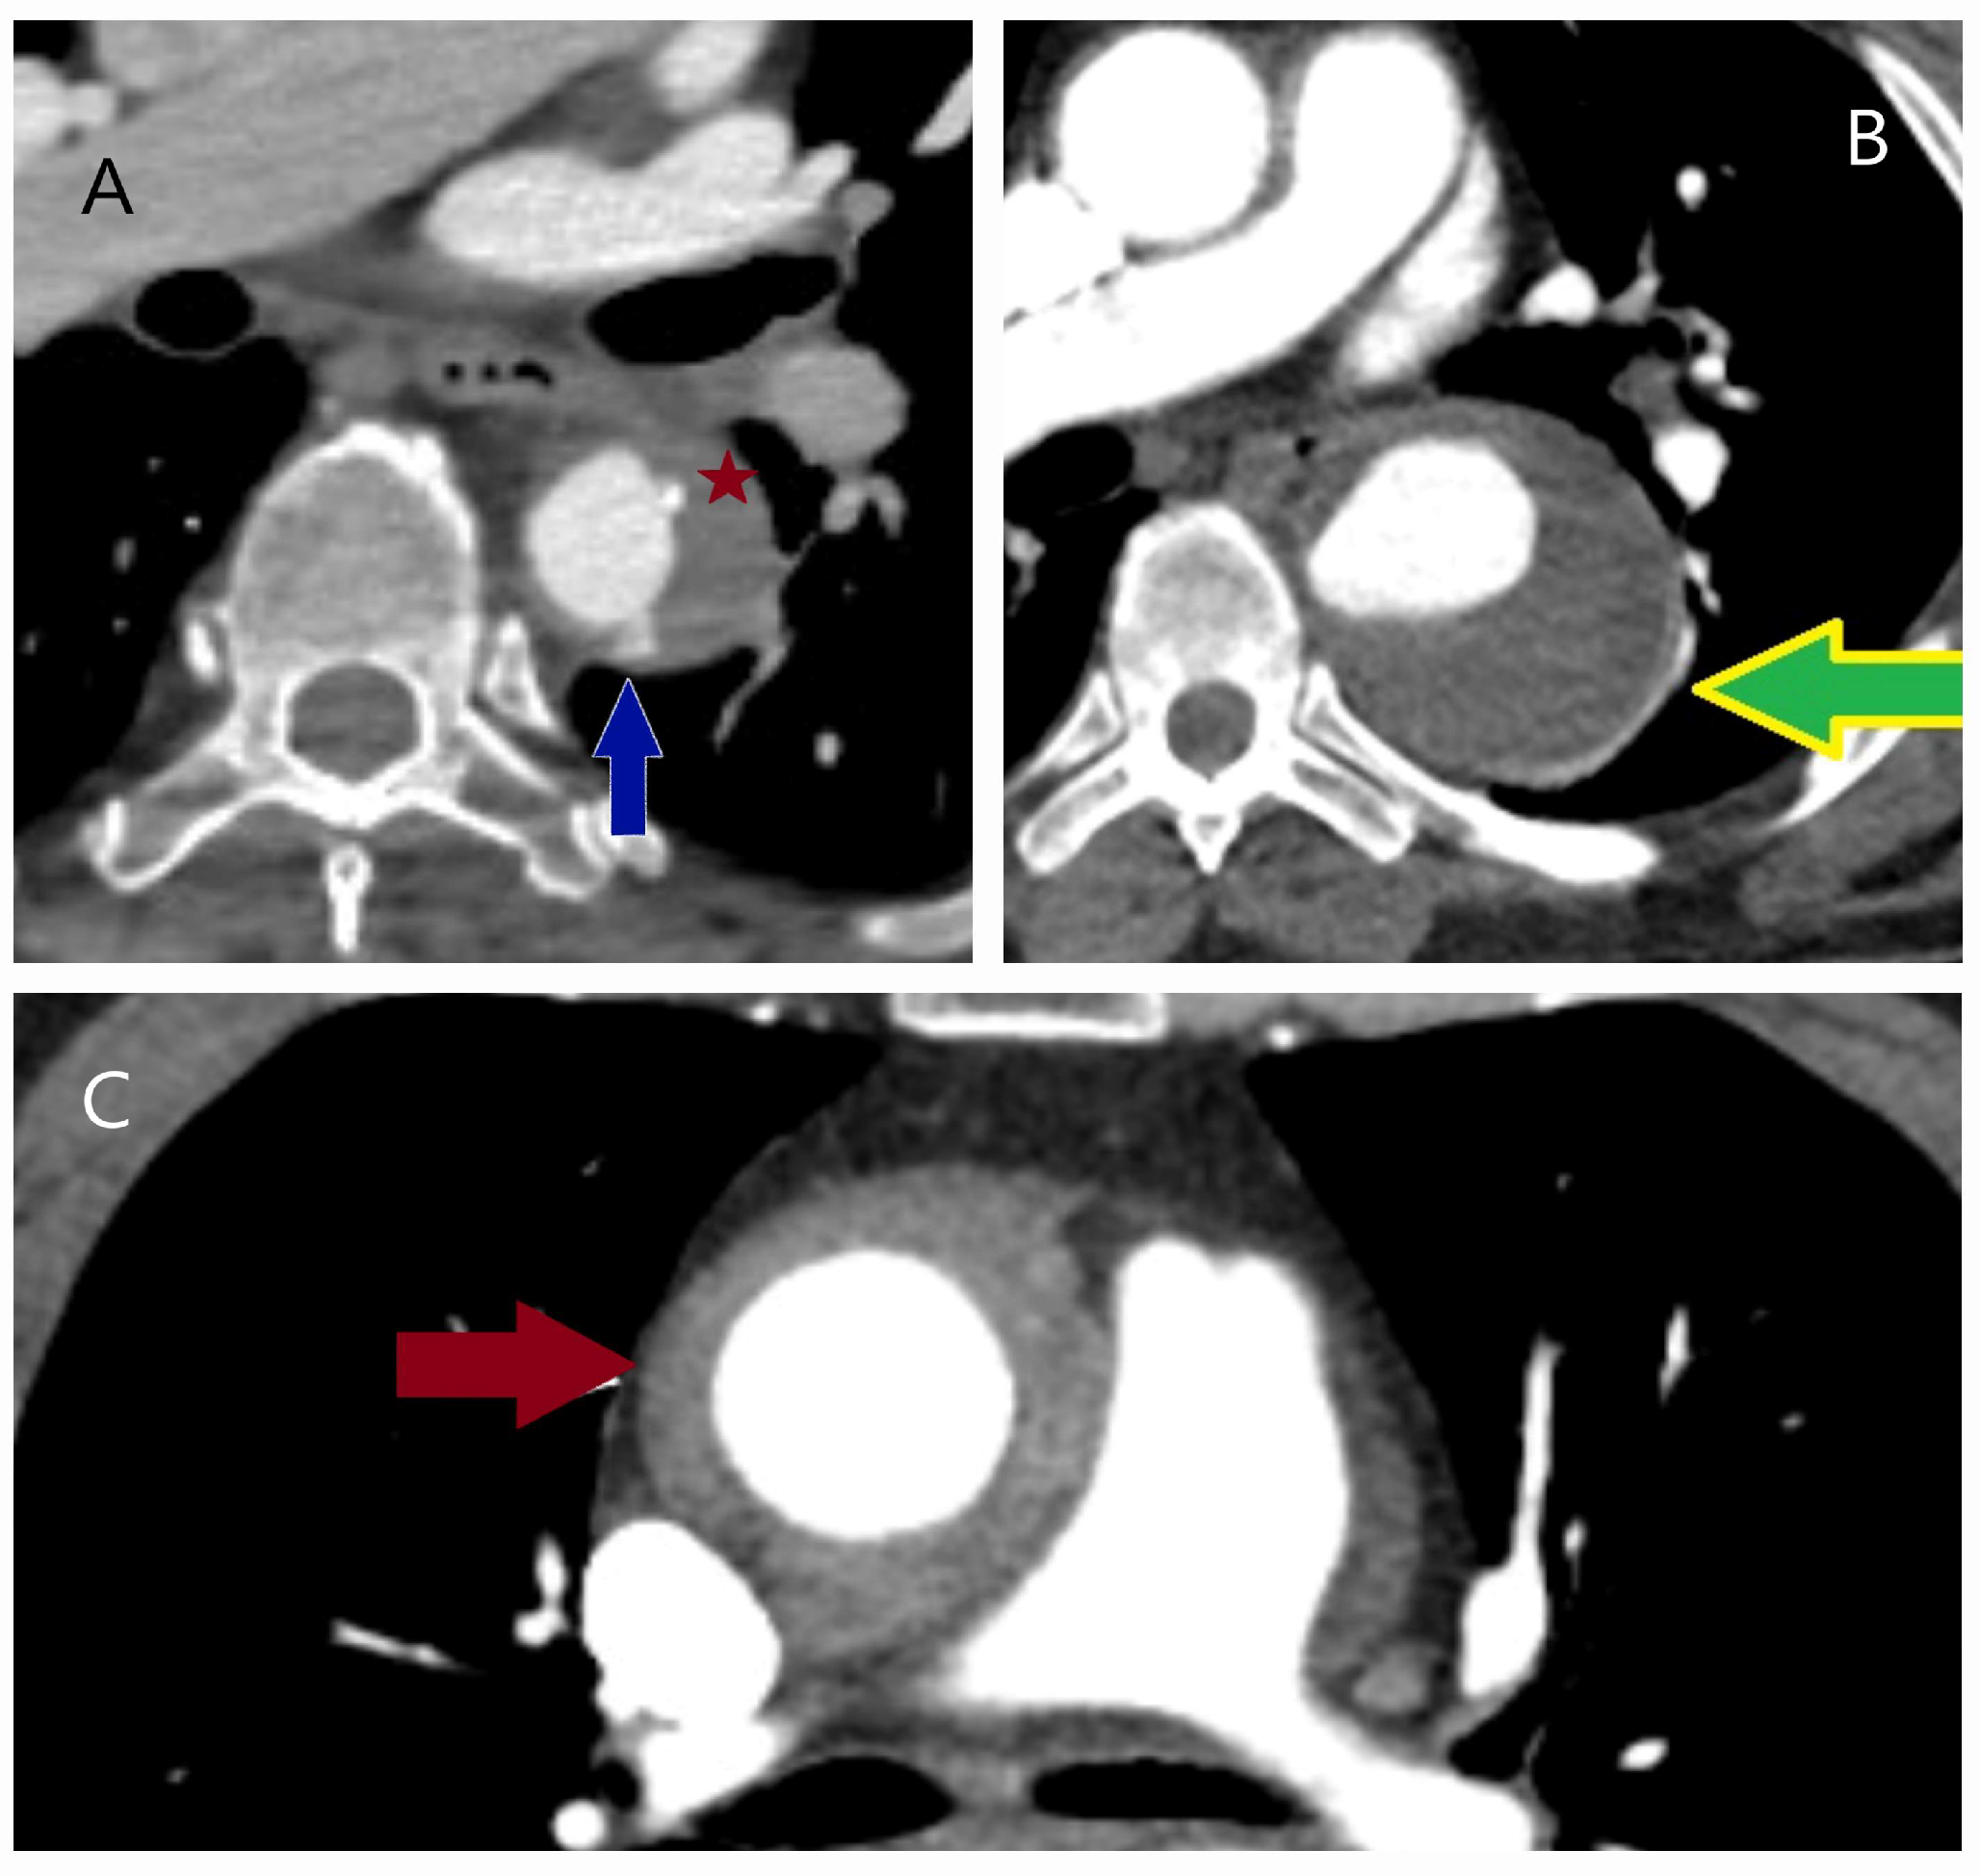

4.1. Dissection, Intramural Hematoma, and Penetrating Aortic Ulcer

5.2.3. Computed Tomography